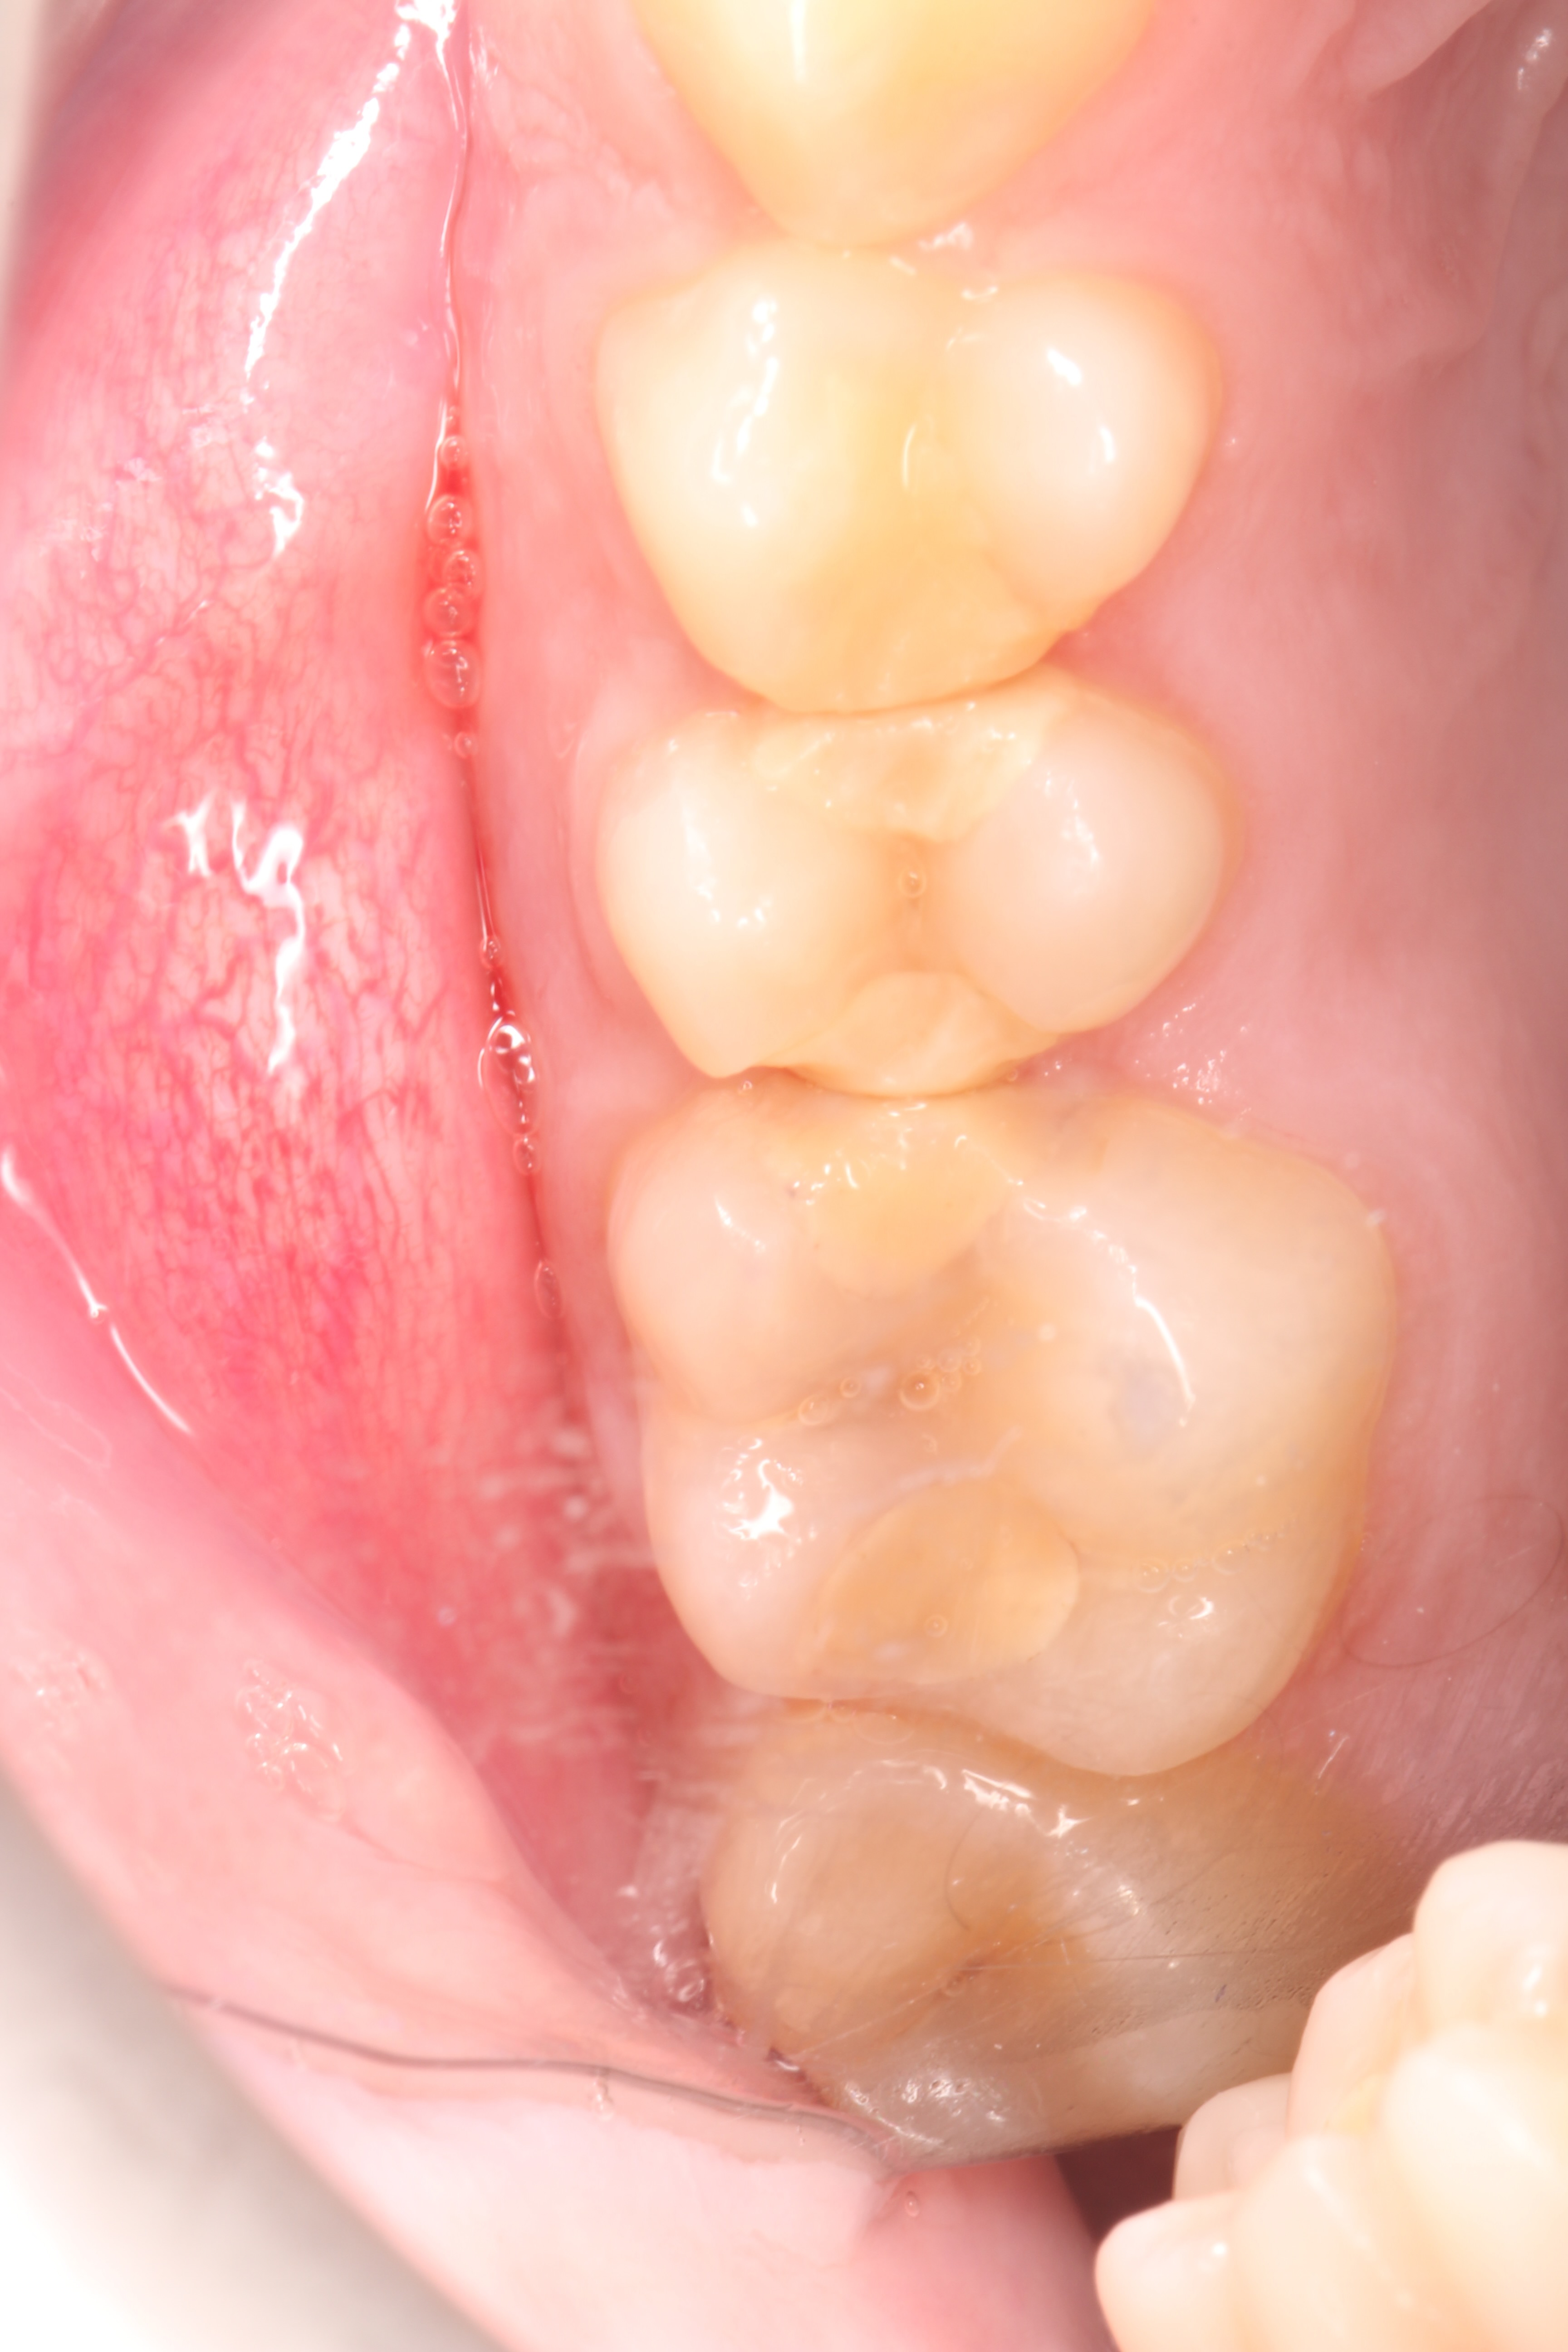

These included team building, communication, photography, endodontics, composite and amalgam restorations, oral surgery, prosthodontics and paediatric dentistry Through these courses I was able to improve on my knowledge and skills from university and implement them in my everyday practice. I have also been keeping a photographic record of my work throughout this year which allows me to reflect on what went well and what I can improve on in the future. space to display your timeline of professional development